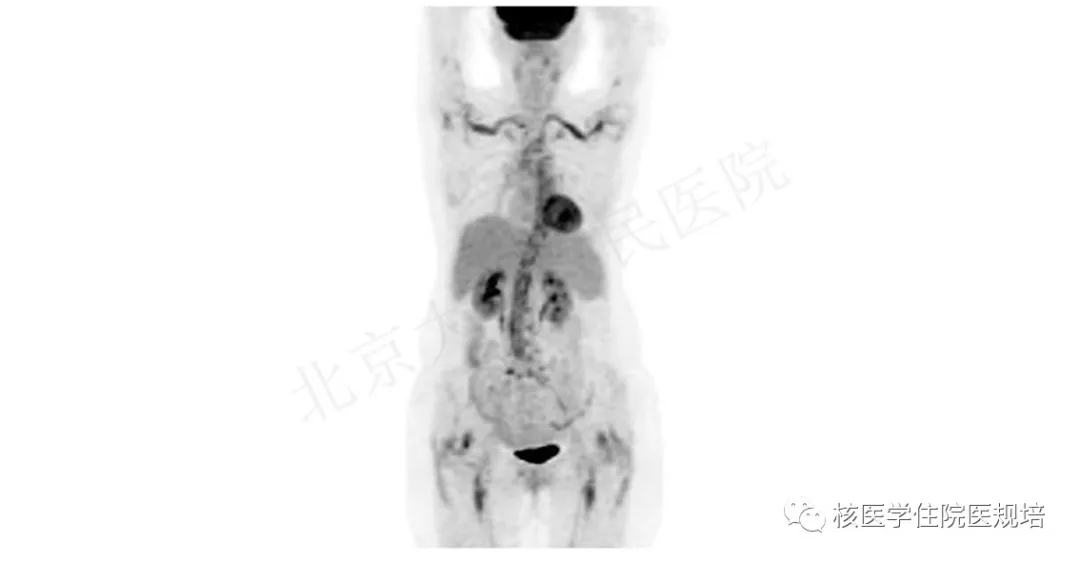

1.患者的FDG PET/CT影像

18F-FDG PET/CT显像示:双侧肩关节、肘关节、髋关节、膝关节可见沿滑膜分布的FDG高摄取,CT见相应区域关节滑膜增生;脊柱多个腰椎椎间关节、耻骨前肌腱附着点及双侧坐骨滑囊区域亦可见多发点状或条片状FDG浓聚影,其中坐骨滑囊见增大表现;上述病灶SUVmax分布在1.6-5.1,相应部位CT均未见骨质破坏征象;双侧手部小关节无受累,扫描野内其他区域未见明确异常FDG摄取或结构改变。

FDG PET/CT显像未见明确恶性病变或局灶性感染征象;全身多发滑膜、滑囊及起止点炎,未累及手部小关节,考虑风湿性多肌痛可能性大。